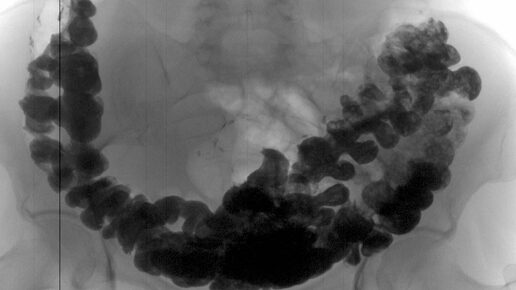

Каловый камень - симптомы и лечение Что такое каловый камень? Причины возникновения, диагностику и методы лечения разберем в статье доктора Аколеловой Евгении Сергеевны, проктолога со стажем в 13 лет. Определение болезни. Причины заболевания Каловый камень (Fecal impaction) — это плотное соединение каловых масс, которое формируется в толстой кишке и мешает нормальному опорожнению кишечника. Такие соединения также называют копролитами. Чаще всего каловые камни появляются на фоне хронического запора, особенно у пожилых, ослабленных и малоподвижных пациентов, а также при нарушении работы тазовых органов (например, после инсульта или травм позвоночника). Иногда каловый камень называют копростазом, но это не совсем точный термин. Под копростазом подразумевают длительный запор, после которого не всегда образуются копролиты. Факторы развития калового камня Основные факторы формирования копролитов: замедленное прохождение пищи в кишечнике, например болезнь Паркинсона; дефицит жидкости в организме — обезвоживание, недостаточное употребление или повышенная потеря жидкости; нарушение процесса выведения кала из организма — дискоординация мышц тазового дна при дефекации (диссинергическая дефекация) [11]; ослабленные мышцы органов пищеварения из-за малоподвижного образа жизни, например у лежачих пациентов с заболеваниями нервной или костно-суставной системы. Формированию калового камня обычно предшествует запор. Различают первичный и вторичный запор. Первичный запор развивается при врождённых или приобретённых болезнях самого кишечника, вторичный запор связан с проблемами других органов и систем, которые влияют на кишечник. Поэтому к факторам, которые способствуют развитию калового камня, также относятся: особенности питания — низкое содержание клетчатки в рационе, нарушение режима; полная или частичная механическая закупорка просвета кишки — раковые опухоли, сдавливание кишки извне, воспаление кишечника и др.; болезни нервной системы — опухоли и травмы спинного мозга, инсульт, рассеянный склероз и др.; врождённые пороки развития — болезнь Гиршпрунга, ДЦП; эндокринные нарушения — сахарный диабет, гипотиреоз; расстройства психического поведения — эмоциональные расстройства, анорексия и др.; болезни соединительной ткани — дерматомиозит, системная склеродермия и др.; приём наркотических обезболивающих (опиоидов); одновременный приём большого количества лекарств или конкретных медикаментов, которые могут напрямую повлиять на пищеварительную систему — антидепрессантов, блокаторов кальциевых каналов, препаратов соединения железа. Также описаны случаи формирования каловых камней из семян растений и различных инородных тел в кишечнике (например, камней из других органов): они становятся ядром, вокруг которого формируется каловый камень. Такие конкременты называют безоарами [13]. Помимо вышеперечисленных факторов развитию калового камня способствует мегаколон: когда толстый кишечник расширяется, транзит каловых масс по нему увеличивается. При обнаружении схожих симптомов проконсультируйтесь у врача. Не занимайтесь самолечением - это опасно для вашего здоровья! Симптомы калового камня Образованию калового камня предшествуют симптомы запора: частота стула сокращается до трёх раз в неделю и менее. Больным может казаться, что опорожнение было неполным, у них появляются постоянные позывы на дефекацию. При испражнении пациентам приходится чрезмерно натуживаться и иногда помогать себе руками. Они начинают принимать слабительное и использовать очистительные клизмы. Стул становится твёрдым или комковатым, его общий объём уменьшается. При формировании калового камня больные могут испытывать повышенное вздутие и боли в животе, а также общее недомогание. Если каловый камень находится в прямой кишке, могут появиться симптомы «ложного» недержания — непроизвольного подтекания каловых масс (энкопрез). Нередко пациенты обращаются в больницу именно с этой проблемой, а не по причине запора. Это происходит из-за того, что копролит забивает прямую кишку, расширяет её ампулу и более жидкий кал, поступающий сверху, просачиваются наружу